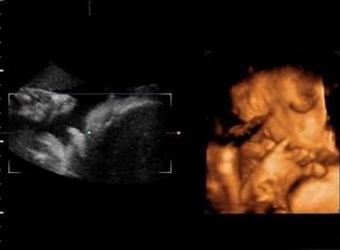

网上流传了很多使用四维彩超来推测男女的方法,其中就有人说四维成像的时候胎儿手呈握拳状一般都是男孩,那么这种说法可信吗,胎儿为什么会双手握拳?更多关于…

在国外据说有根据NT超声的图片来判断男女的方法,外国人称这种判断法为nub theory,那么英国nub原理看男女准不准呢,nub平行一定是女宝吗?更多关于生男生女的…

在国外有通过宝宝的超声图来判断男女性别的办法,也就是nub点看男女,那么12周男宝宝特点NT值是什么呢,用nub点看男女准不准?更多关于生男生女的相关内容尽在…